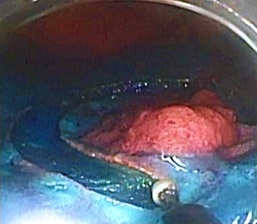

剥離終了

切除検体画像